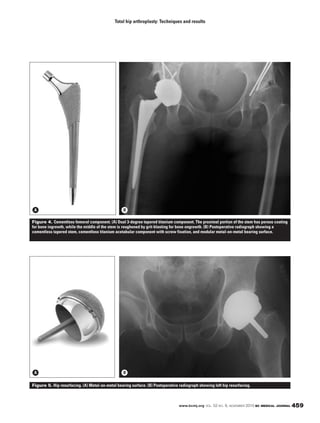

Figure 1. Cruciate ligament retaining

implant.

Figure 2. Posterior stabilized implant. The

presence of a post (arrow) distinguishes this

design from the cruciate ligament retaining

design in Figure 1, which has no such post.

Figure 3. Posterior stabilized implant

with larger post (arrow) for improving

coronal plane stability.

Figure 4. Hinged implant for improving

coronal plane stability. The hinge is linked

into the femoral component as indicated by

the arrow.

signs, from cruciate ligament retain-

ing ( ) and posterior stabilized

( ) implants that usually pro-

vide sufficient stability in the primary

setting, through to megaprotheses for

replacing tumor or bone.

The level of built-in constraint, or

stability,requiredbyakneeprostheses

depends upon whether the posterior

cruciate and collateral ligaments are

intact. If the posterior cruciate liga-

ment is compromised, as it is in most

rheumatoid knees, or there is fixed

Figure 2

Figure 1

( ). If the medial collateral lig-

ament is compromised, a hinged pros-

thesis is chosen to further improve

coronal plane stability ( ). In-